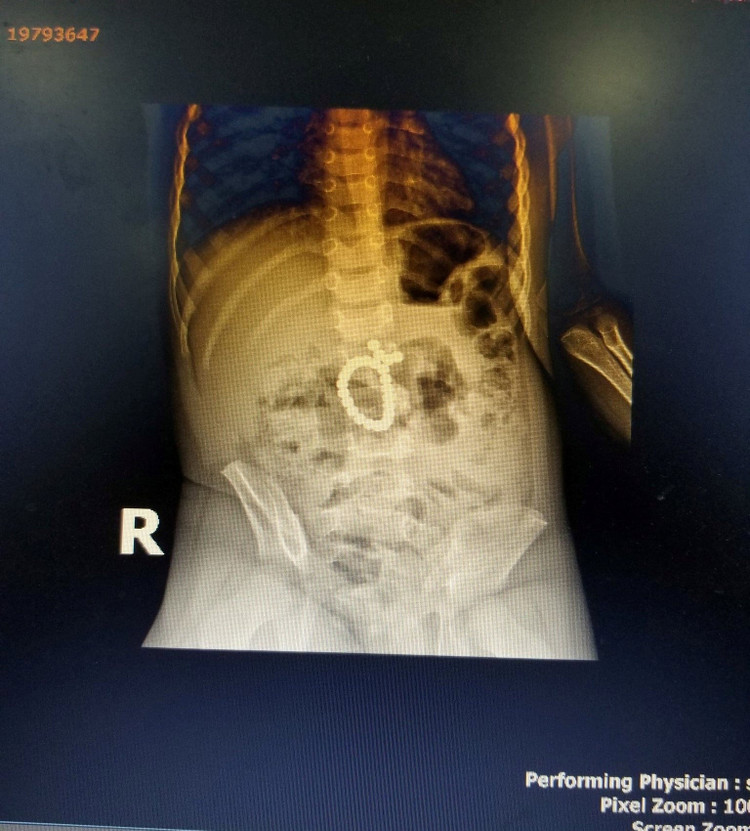

Hình ảnh những viên nam châm dính nhau trong ổ bụng bệnh nhi

Trong quá trình phẫu thuật, các bác sĩ đã phát hiện 25 viên bi nam châm dính chặt vào nhau gây tắc nghẽn ruột, khiến tá tràng và ruột bệnh nhi thủng nhiều vị trí.